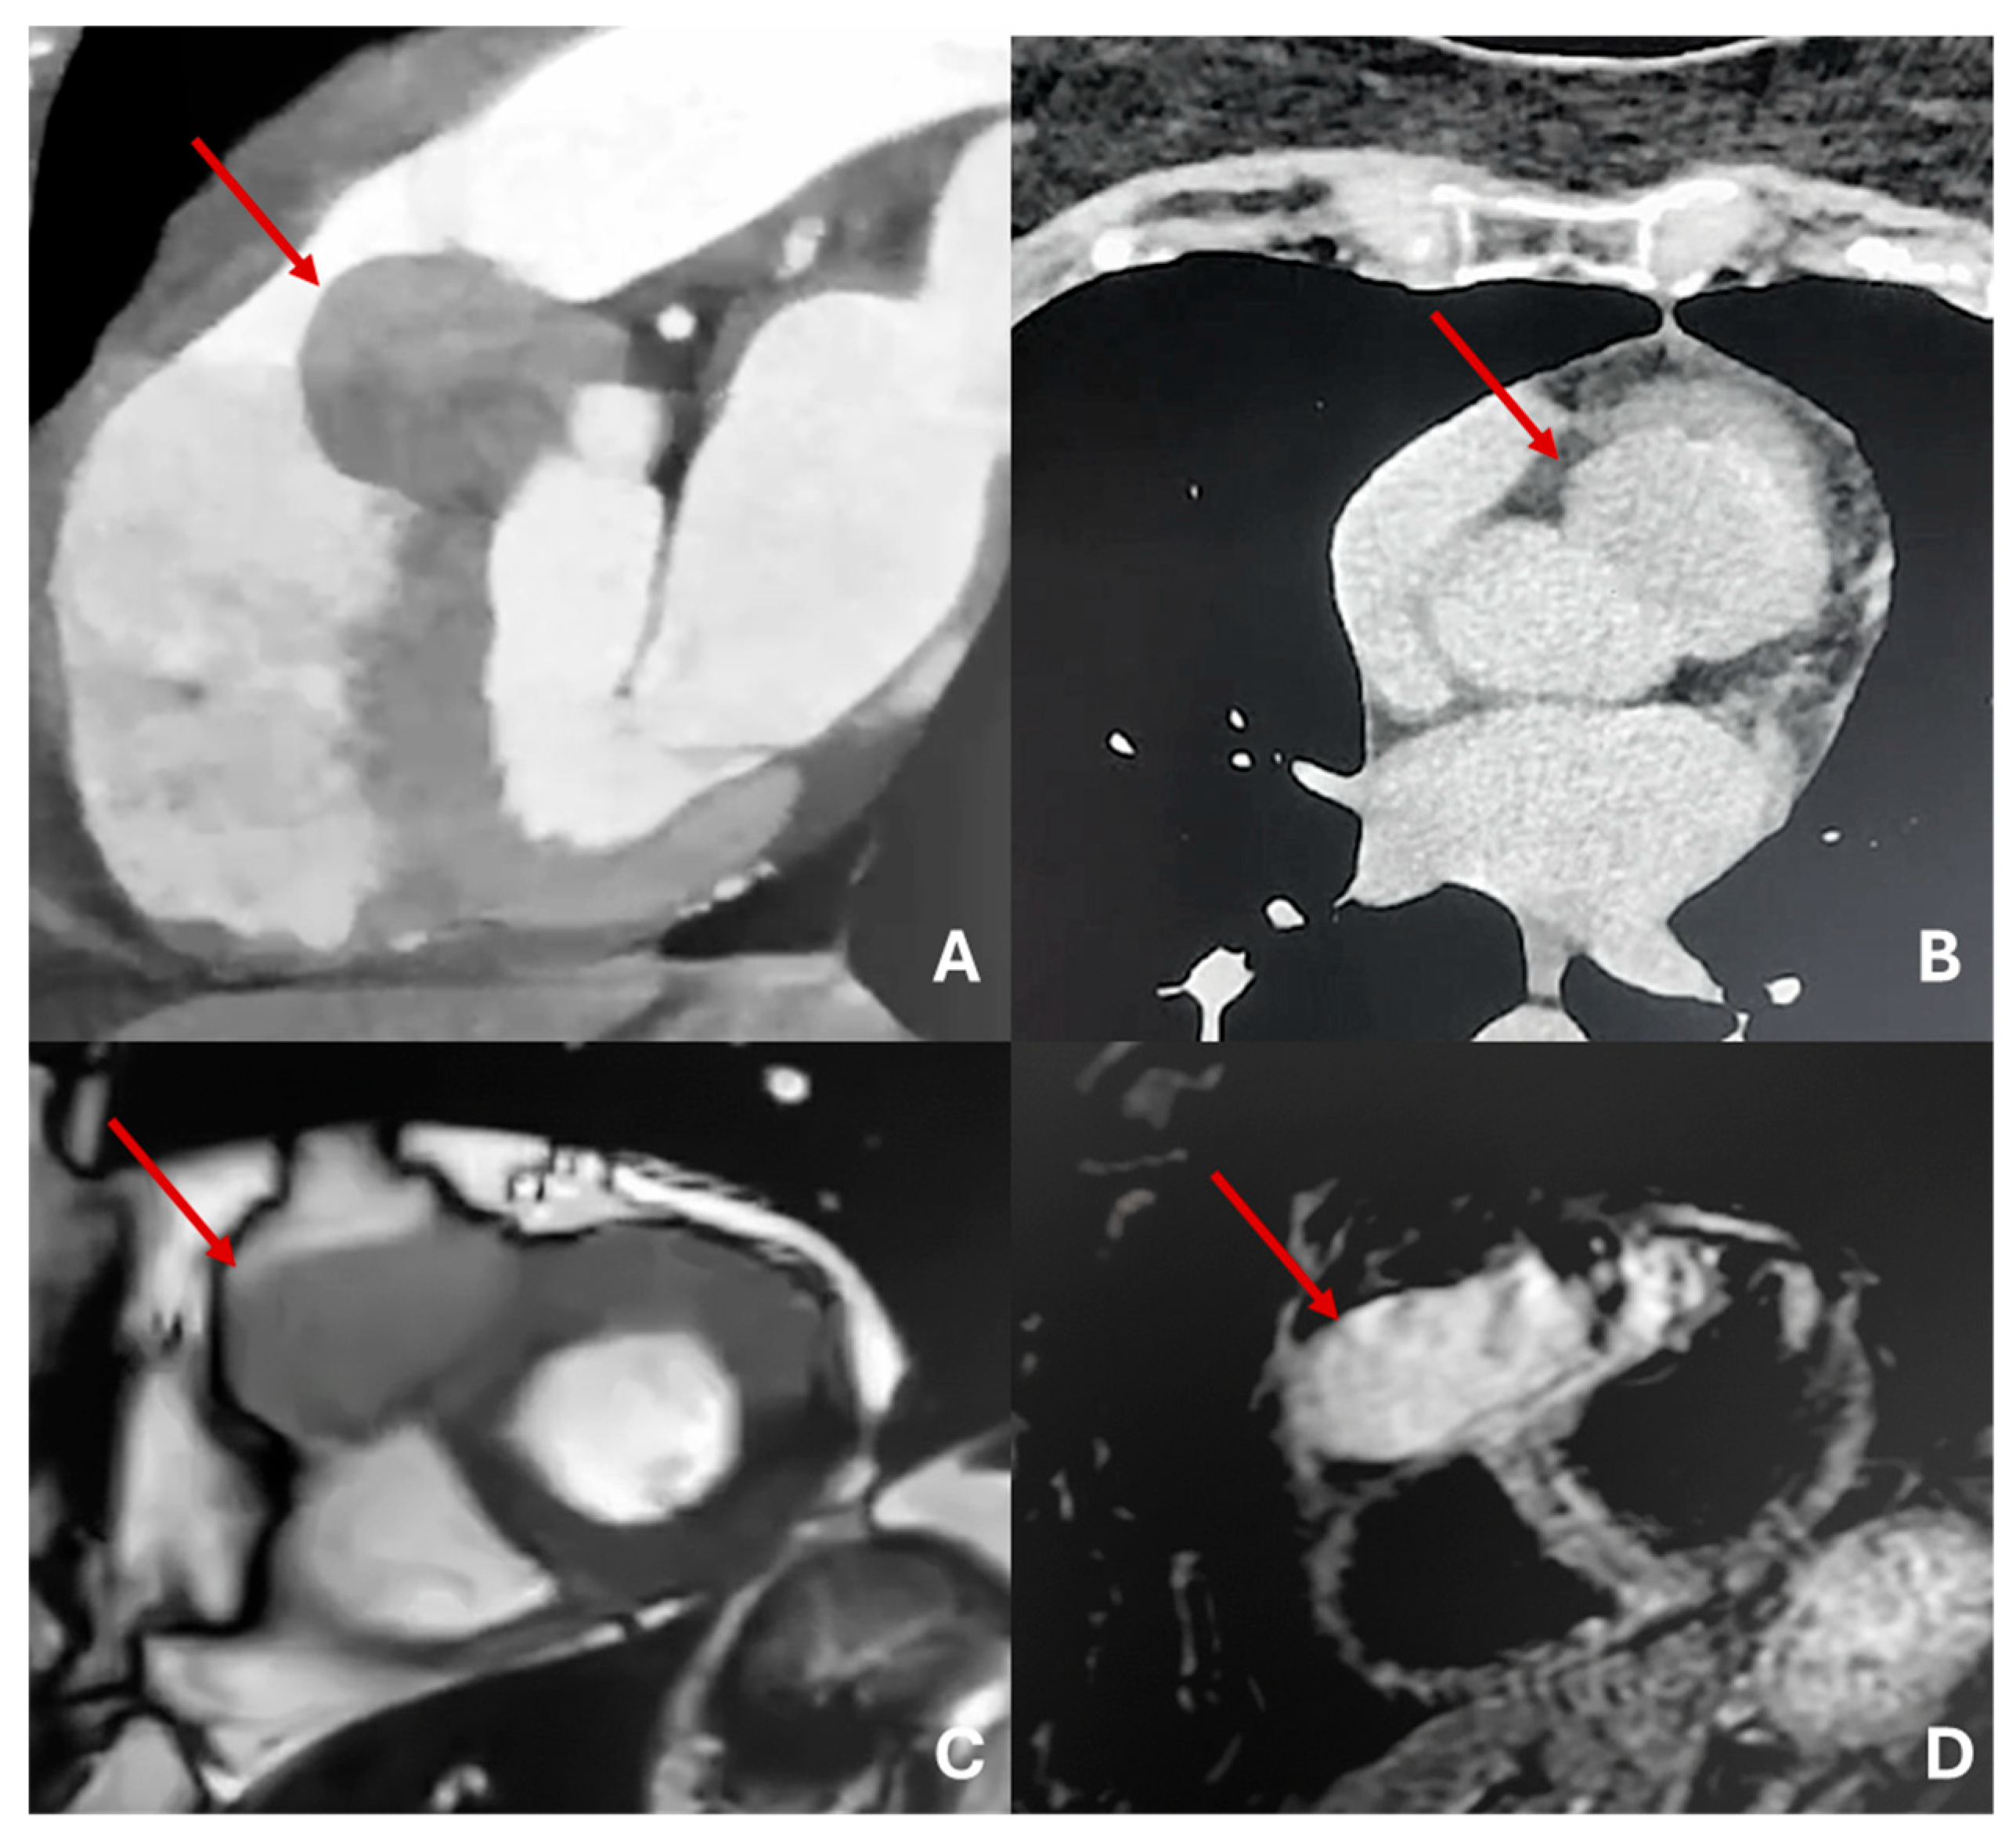

Figure 11. Giant hemangioma originating from the anterior-basal interventricular septum, as seen on CT (A), showing progressive and intense enhancement on delayed post-contrast CT acquisition (B). The lesion demonstrates heterogeneous hypointensity on T2-steady state-weighted MRI (C), marked hyperintensity on fat-saturated T2-weighted images (D).

Figure 12. Massive sarcoma of anterior-lateral wall of left ventricle with massive pericardial effusion and left pulmonary lobe metastases. Isodense in T2-weighted images (A) and T1 (B) with inhomogeneous LGE (C).

5.7. Hemangioma

Cardiac hemangiomas are rare vascular malformations made up of clusters of endothelial-lined channels separated by thin fibrous and fatty septa. Typically asymptomatic, they can nonetheless cause pericardial effusion, innocuous murmurs, arrhythmias, tamponade, cardiac arrest or even sudden death. Histologically they fall into capillary, cavernous or arteriovenous types and may involve any layer of the heart muscle, most commonly the left atrium. On echocardiography they appear as hyperechogenic masses; CT at baseline shows heterogeneous density that becomes markedly hyperenhanced after intravenous contrast; and MRI reveals a heterogeneous lesion that is iso- to hyperintense on T1-weighted sequences, intensely hyperintense on T2-weighted images, with equally heterogeneous contrast uptake [22,46,47].